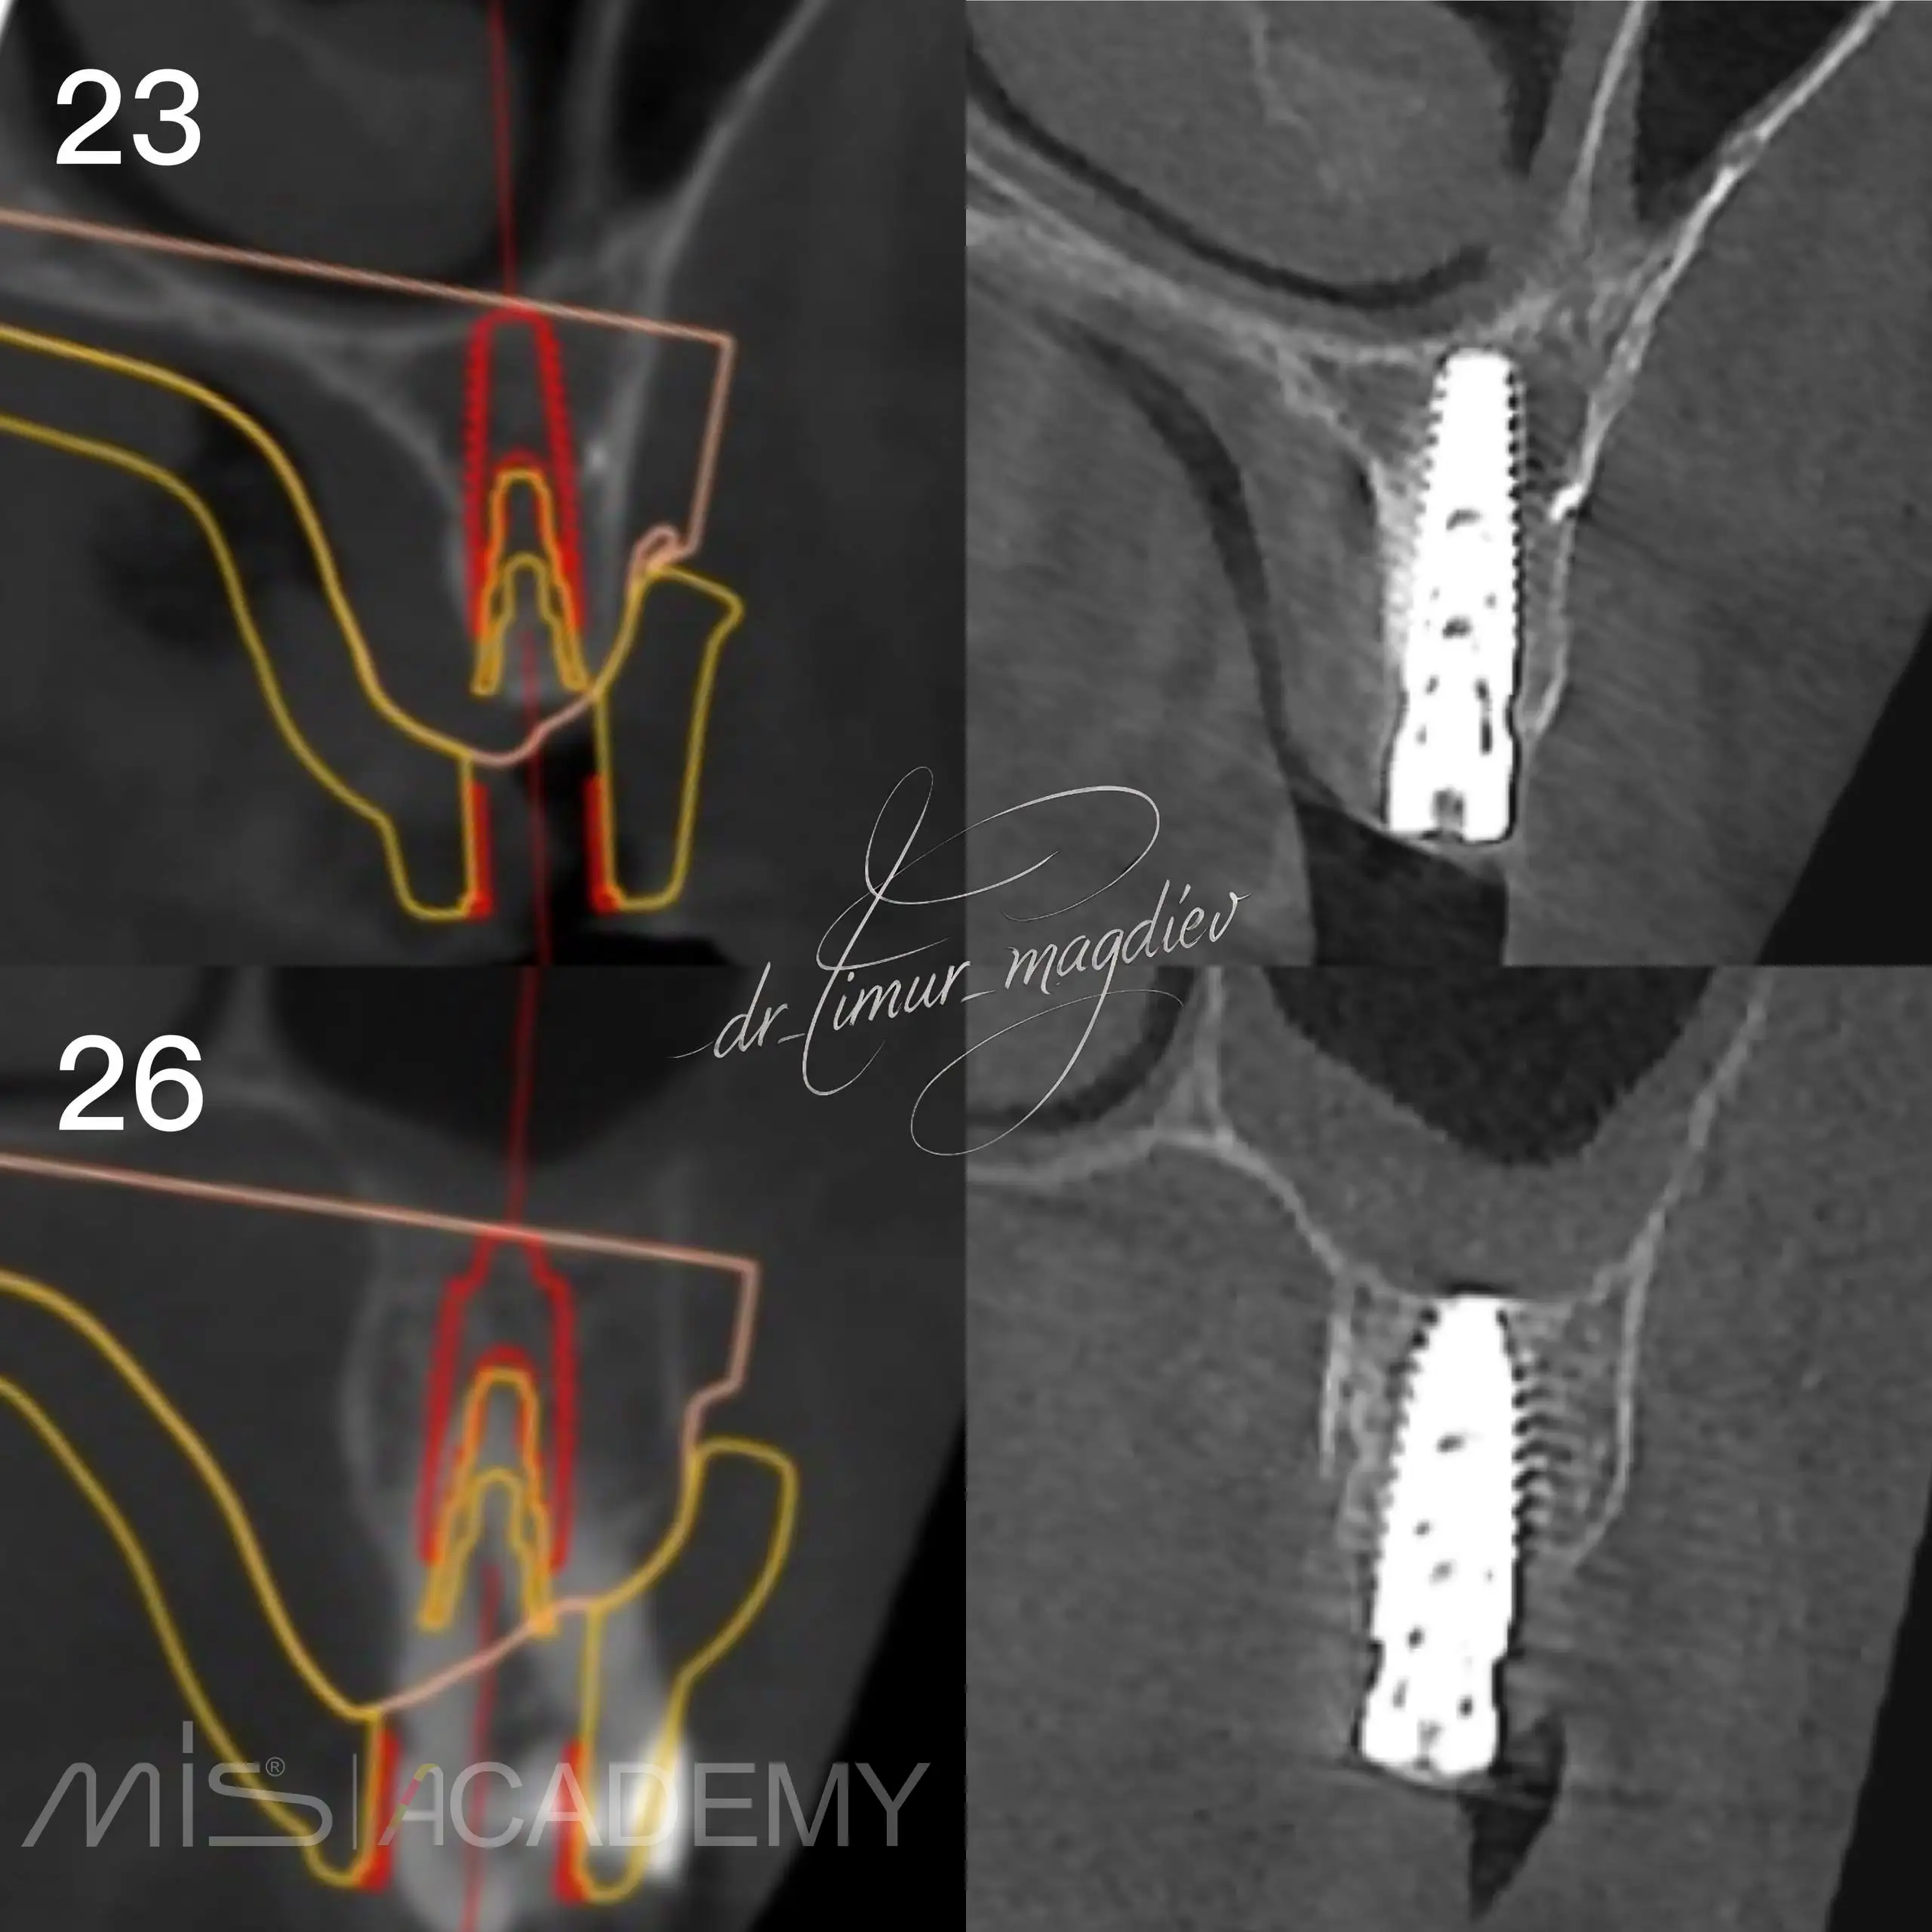

Комплексная реабилитация пациента; в полном навигационном протоколе:

— Установлены имплантаты MIS C1 + Connect абатменты.